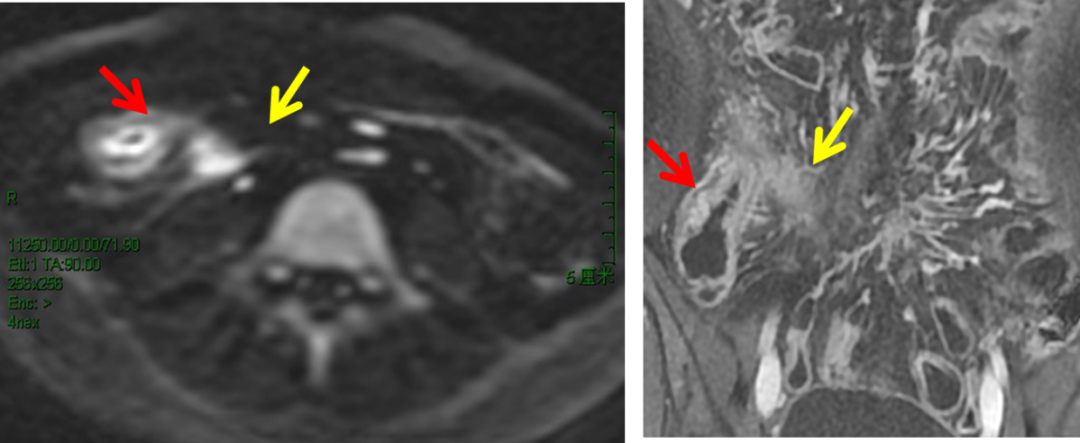

肠壁显著增厚、靶样强化、肠腔内弥漫息肉样增生,DWI 中见肠壁全层信号增高,提示病灶活动。 医学百科网 | YxBaike.Com

DWI 扫描显示病变肠段粘膜面信号明显增高(红箭头),提示病变处于活动期受累肠段旁脓肿信号明显增高(黄箭头),使病变显示更清晰